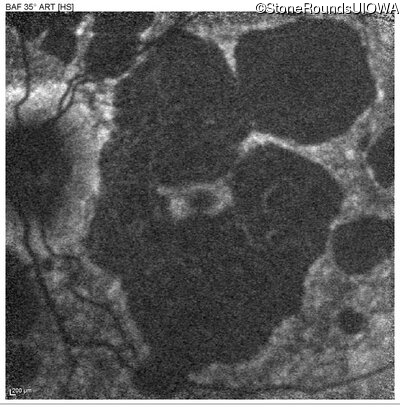

Blue Autofluorescence - Left - 20/40 +1

Exemplar